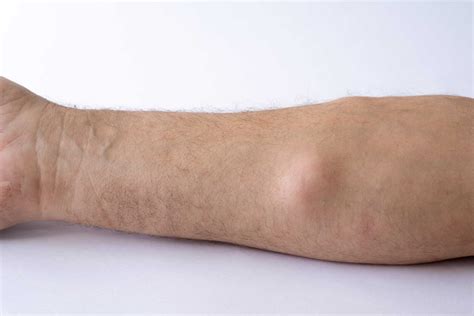

A lipoma is a very common, benign (noncancerous) tumor made up of fat cells. These growths are typically soft, doughy to the touch, and easily movable under the skin. They grow slowly and are most often found in the subcutaneous tissue—the layer of fat just beneath the skin—usually on the neck, shoulders, back, abdomen, or arms.

Consistency Soft, doughy Firm, hard, or irregular

Mobility Freely movable Often fixed or deeply tethered